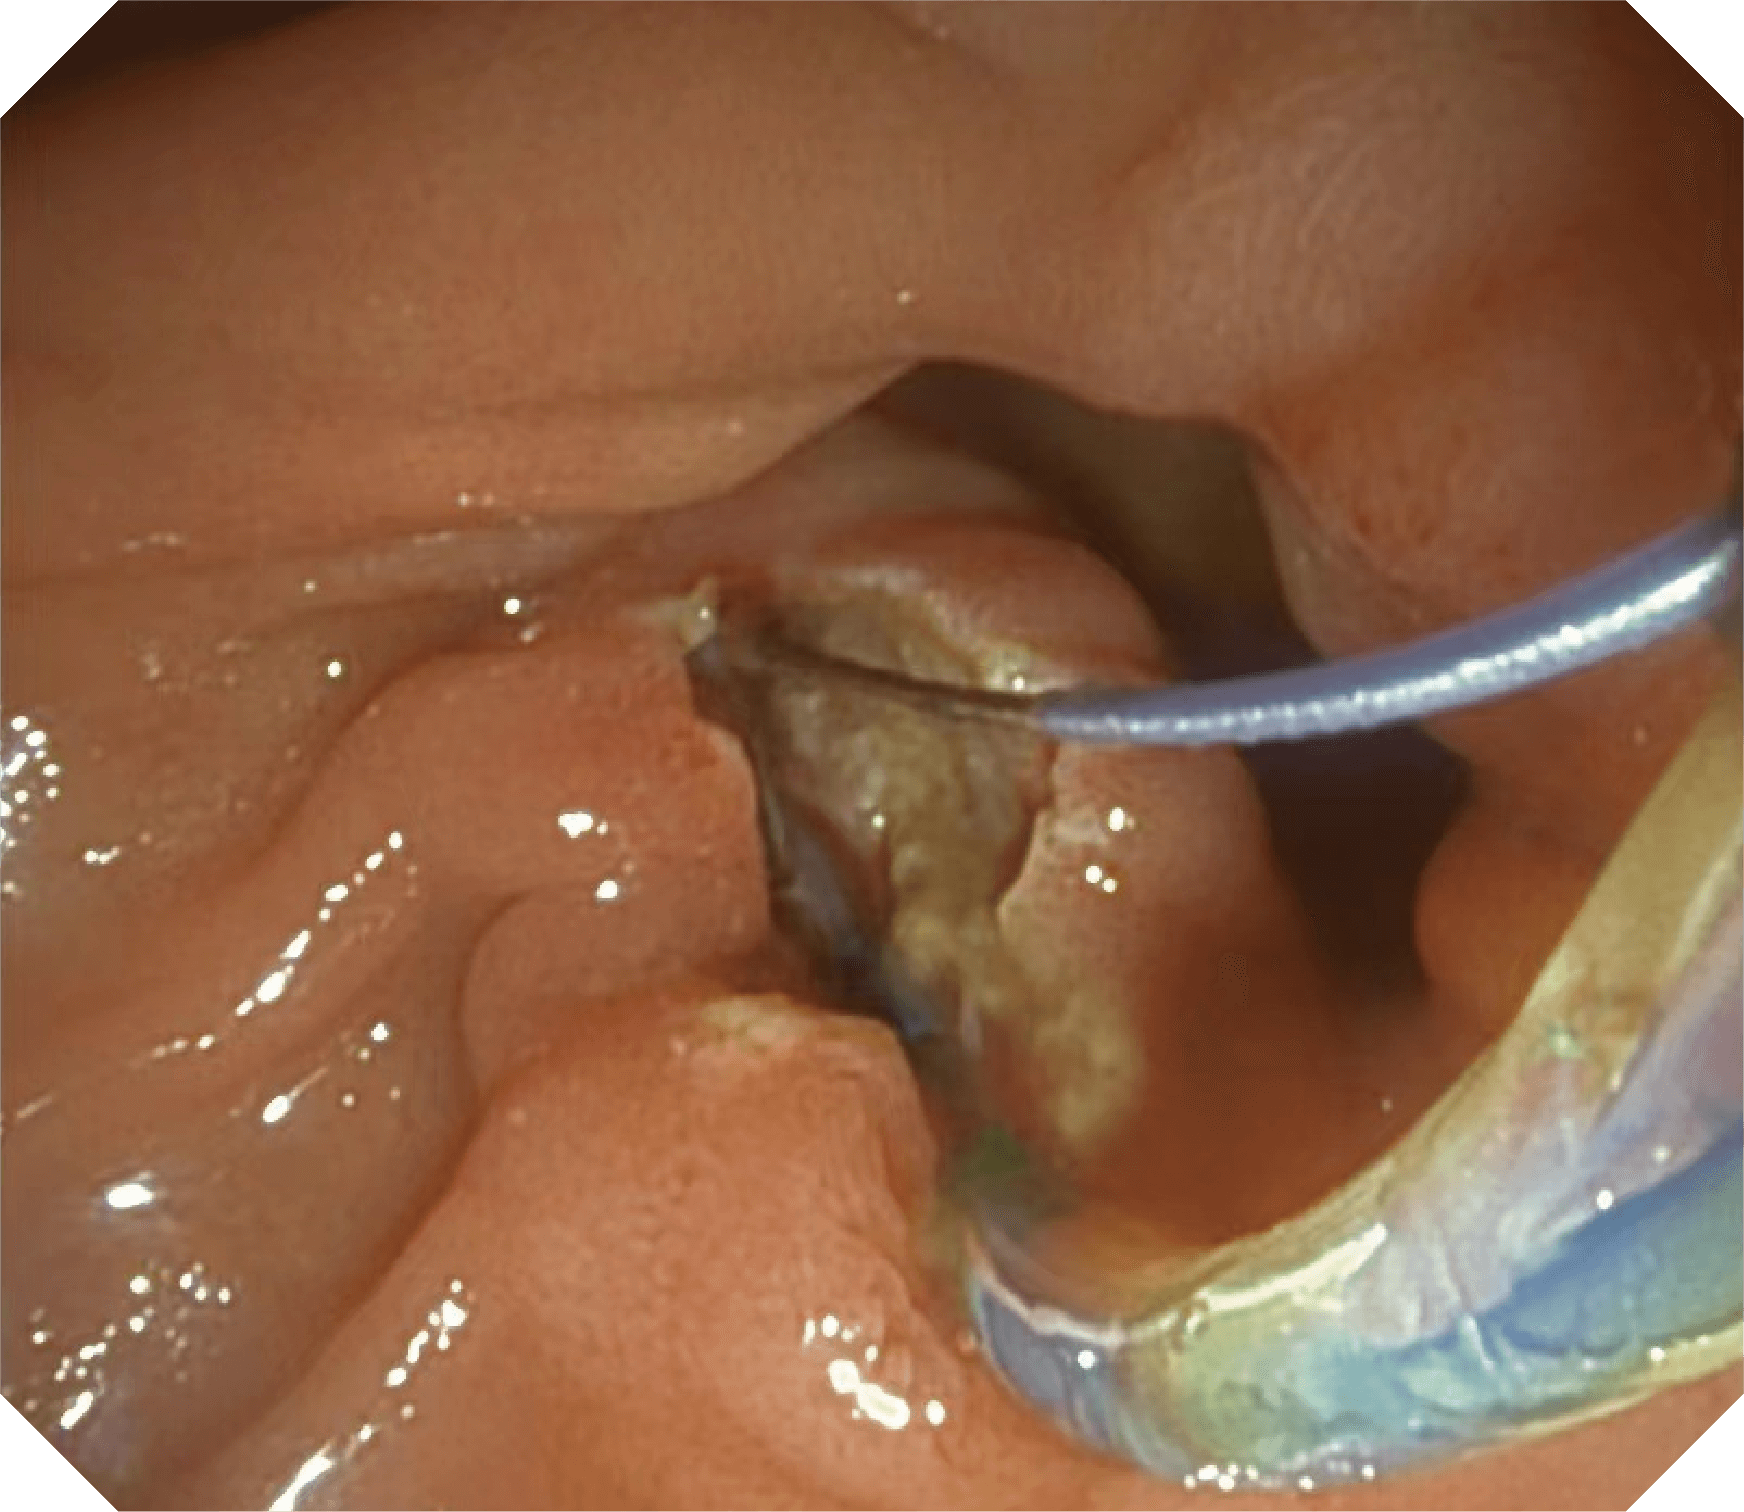

• 器械辅助导向功能

当切开刀伸出视野外时,导向面引导其回归视野